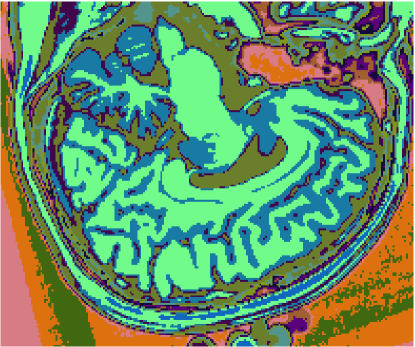

As figuras 2 (banda 0), 3 (banda 1) e 4 (banda 2) mostram a fatia 97 de um volume de imagens sagitais com 181 fatias e 0% de ruído, ponderadas em PD (densidade de próton), T1subscript𝑇1T_{1} e T2subscript𝑇2T_{2}, enquanto a figura 5 ilustra a composição colorida R0-G1-B2 da mesma fatia. Pode-se notar no topo do crânio, na parte inferior das imagens, a presença de artefatos, que podem ser resultantes de erros no simulador, mas que não são prejudiciais à análise, uma vez que, neste trabalho, não é dada ênfase à análise anatômica.

Figura 5: Composição colorida R0-G1-B2 das imagens da fatia 97 ponderadas em PD, T1subscript𝑇1T_{1} e T2subscript𝑇2T_{2}